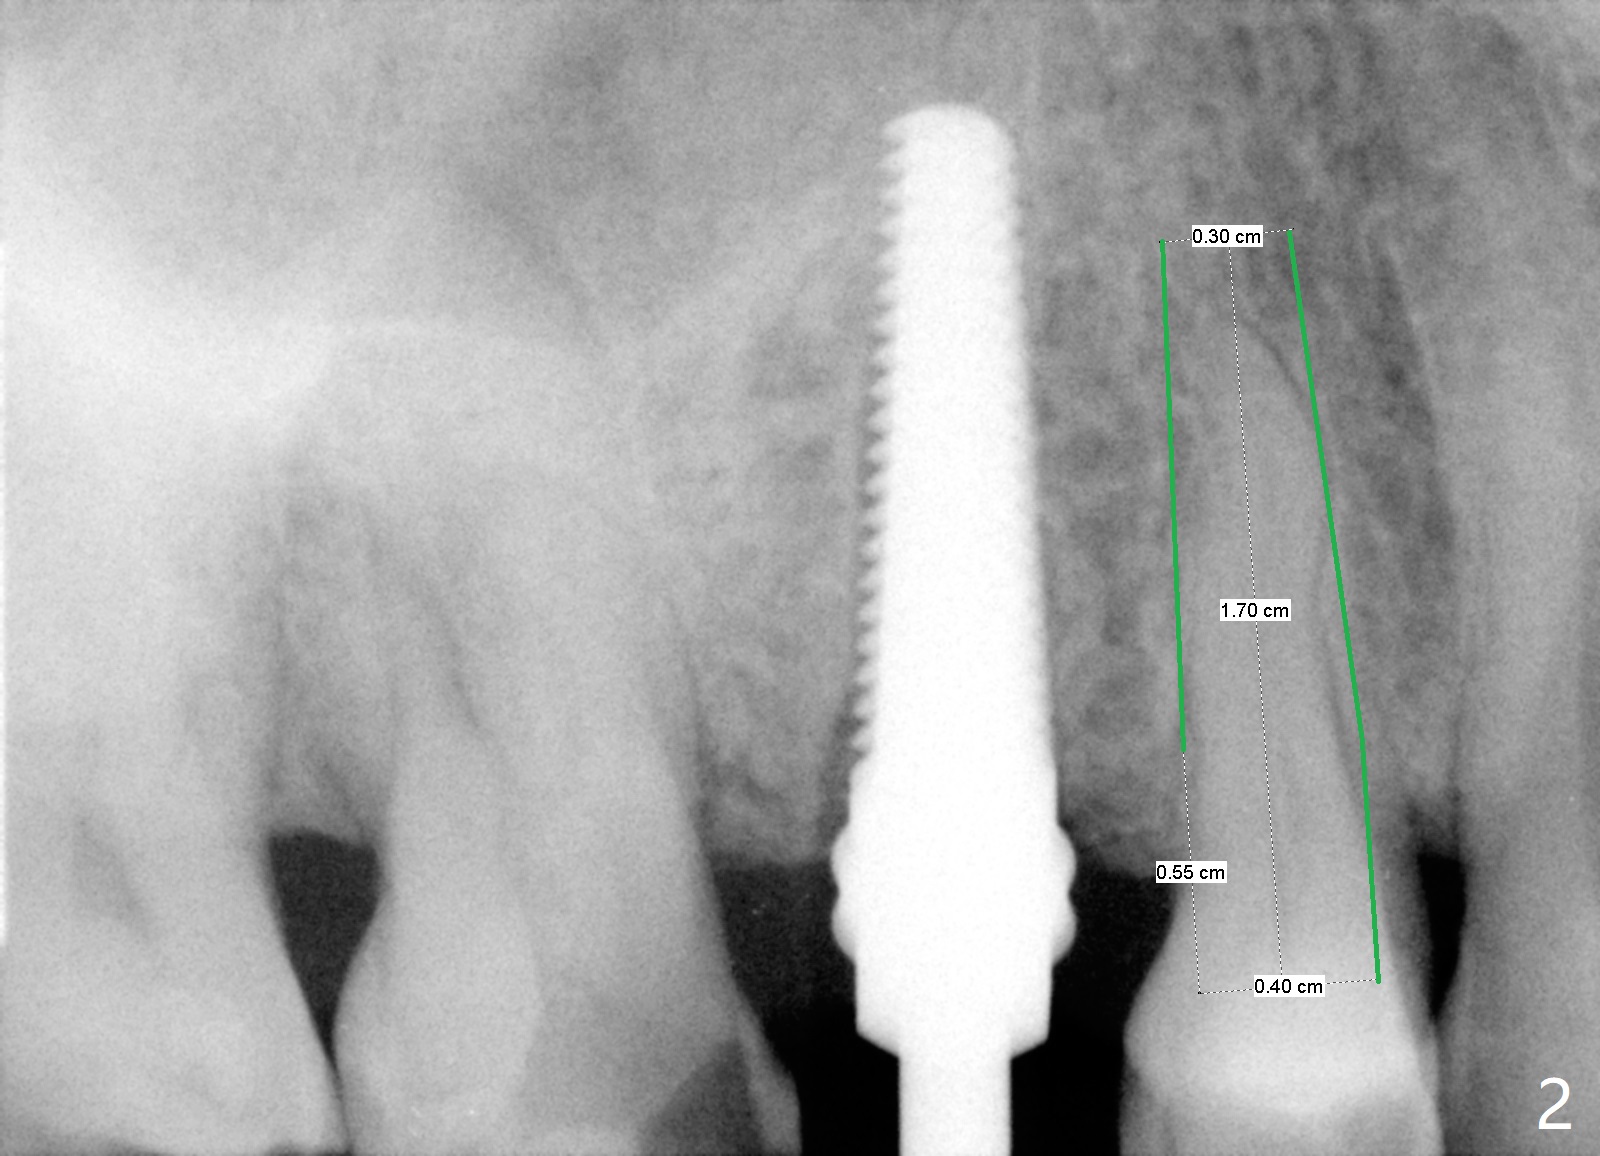

A 78-year-old man with diabetes and recent history of stroke wants to have an implant at #5 (fracture). He was not pleased with the long implant at #4 several years ago with delayed healing. This time he requests a short implant instead (Fig.1,2). Make sure that he has stopped Aspirin.